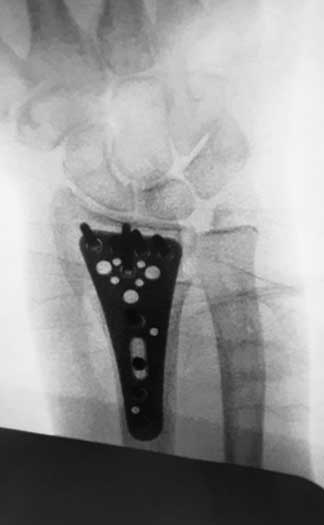

Vasculares, nerviosas, articulares y óseas que se traducen en fracturas conocidas como edema óseo.

Artículo de trabajo con equipo de Primera División “Tuzos de Pachuca”

Durante mi entrenamiento en mi segundo fellow en cirugía articular y lesiones deportivas, tuve la oportunidad de hacer una rotación en el hospital CEMA by FIFA (Centro de Excelencia Médica en Altura) en Pachuca Hidalgo, donde brindé atención médica y quirúrgica en las instalaciones de la Universidad a pacientes deportistas profesionales y de alto rendimiento, miembros del equipo de fútbol “Tuzos de Pachuca”.